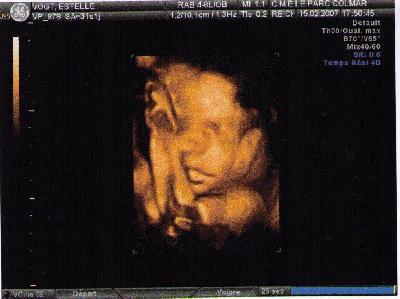

Dans le ventre de sa maman

• échographie

Lisa née le 18 Avril 2007 à 13H27